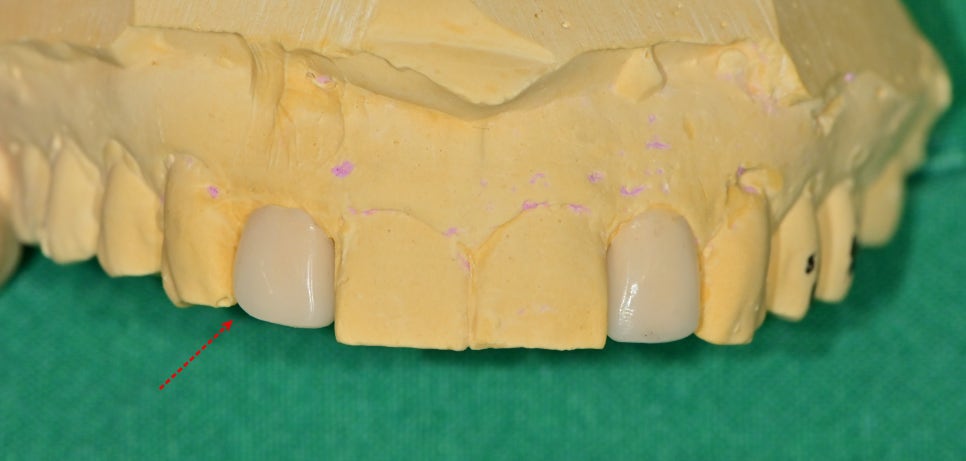

파절 부위에 교합간섭을 피하기 위해

치아 형태가 제작이 되었습니다.

되도록 기존 대문니의 형태와 이질감 없고

대칭적으로 같은 형태가 나오게 최종 보철물을 제작해야 합니다.

이 진단모형에서는 치아 대칭이 이루어지지 않아

진료실에서 모형 수정을 한 후에 이것을

토대로 치아 삭제량을 결정할 수 있는

인덱스를 제작을 하게 됩니다.